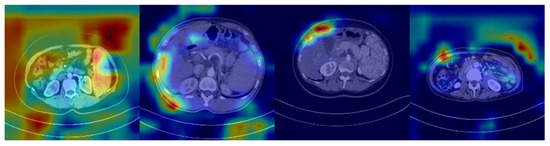

2. Predictive Model

The features potentially seen in CT images may reflect the expression of many genes in HCC patients, including SOX9. Unlike radiomic analyses, deep learning models can automatically identify features in CT images related to SOX9 expression, rather than being limited to known, predefined biomarkers. This enables deep learning models to learn and predict more holistically. However, despite the significant improvement in their classification performance compared to that of traditional machine learning methods, deep learning models are still inevitably affected by noise, especially from features in low-correlation regions. As shown in Figure 1, which presents the heatmap of a SOX9-positive prediction based on ResNet, deeper colors indicate regions receiving higher attention from the model. However, the model tends to focus on noisy areas, which significantly hampers its performance.

Figure 1. Heatmap from a ResNet-based model showing a SOX9-positive prediction, with darker regions indicating more attention from the model.